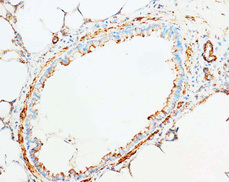

- Main image

- Experimental details

- Paraffi Rat Lung Tissue stained with Cytochrome C Polyclonal Antibody

- Validation comment

- IHC